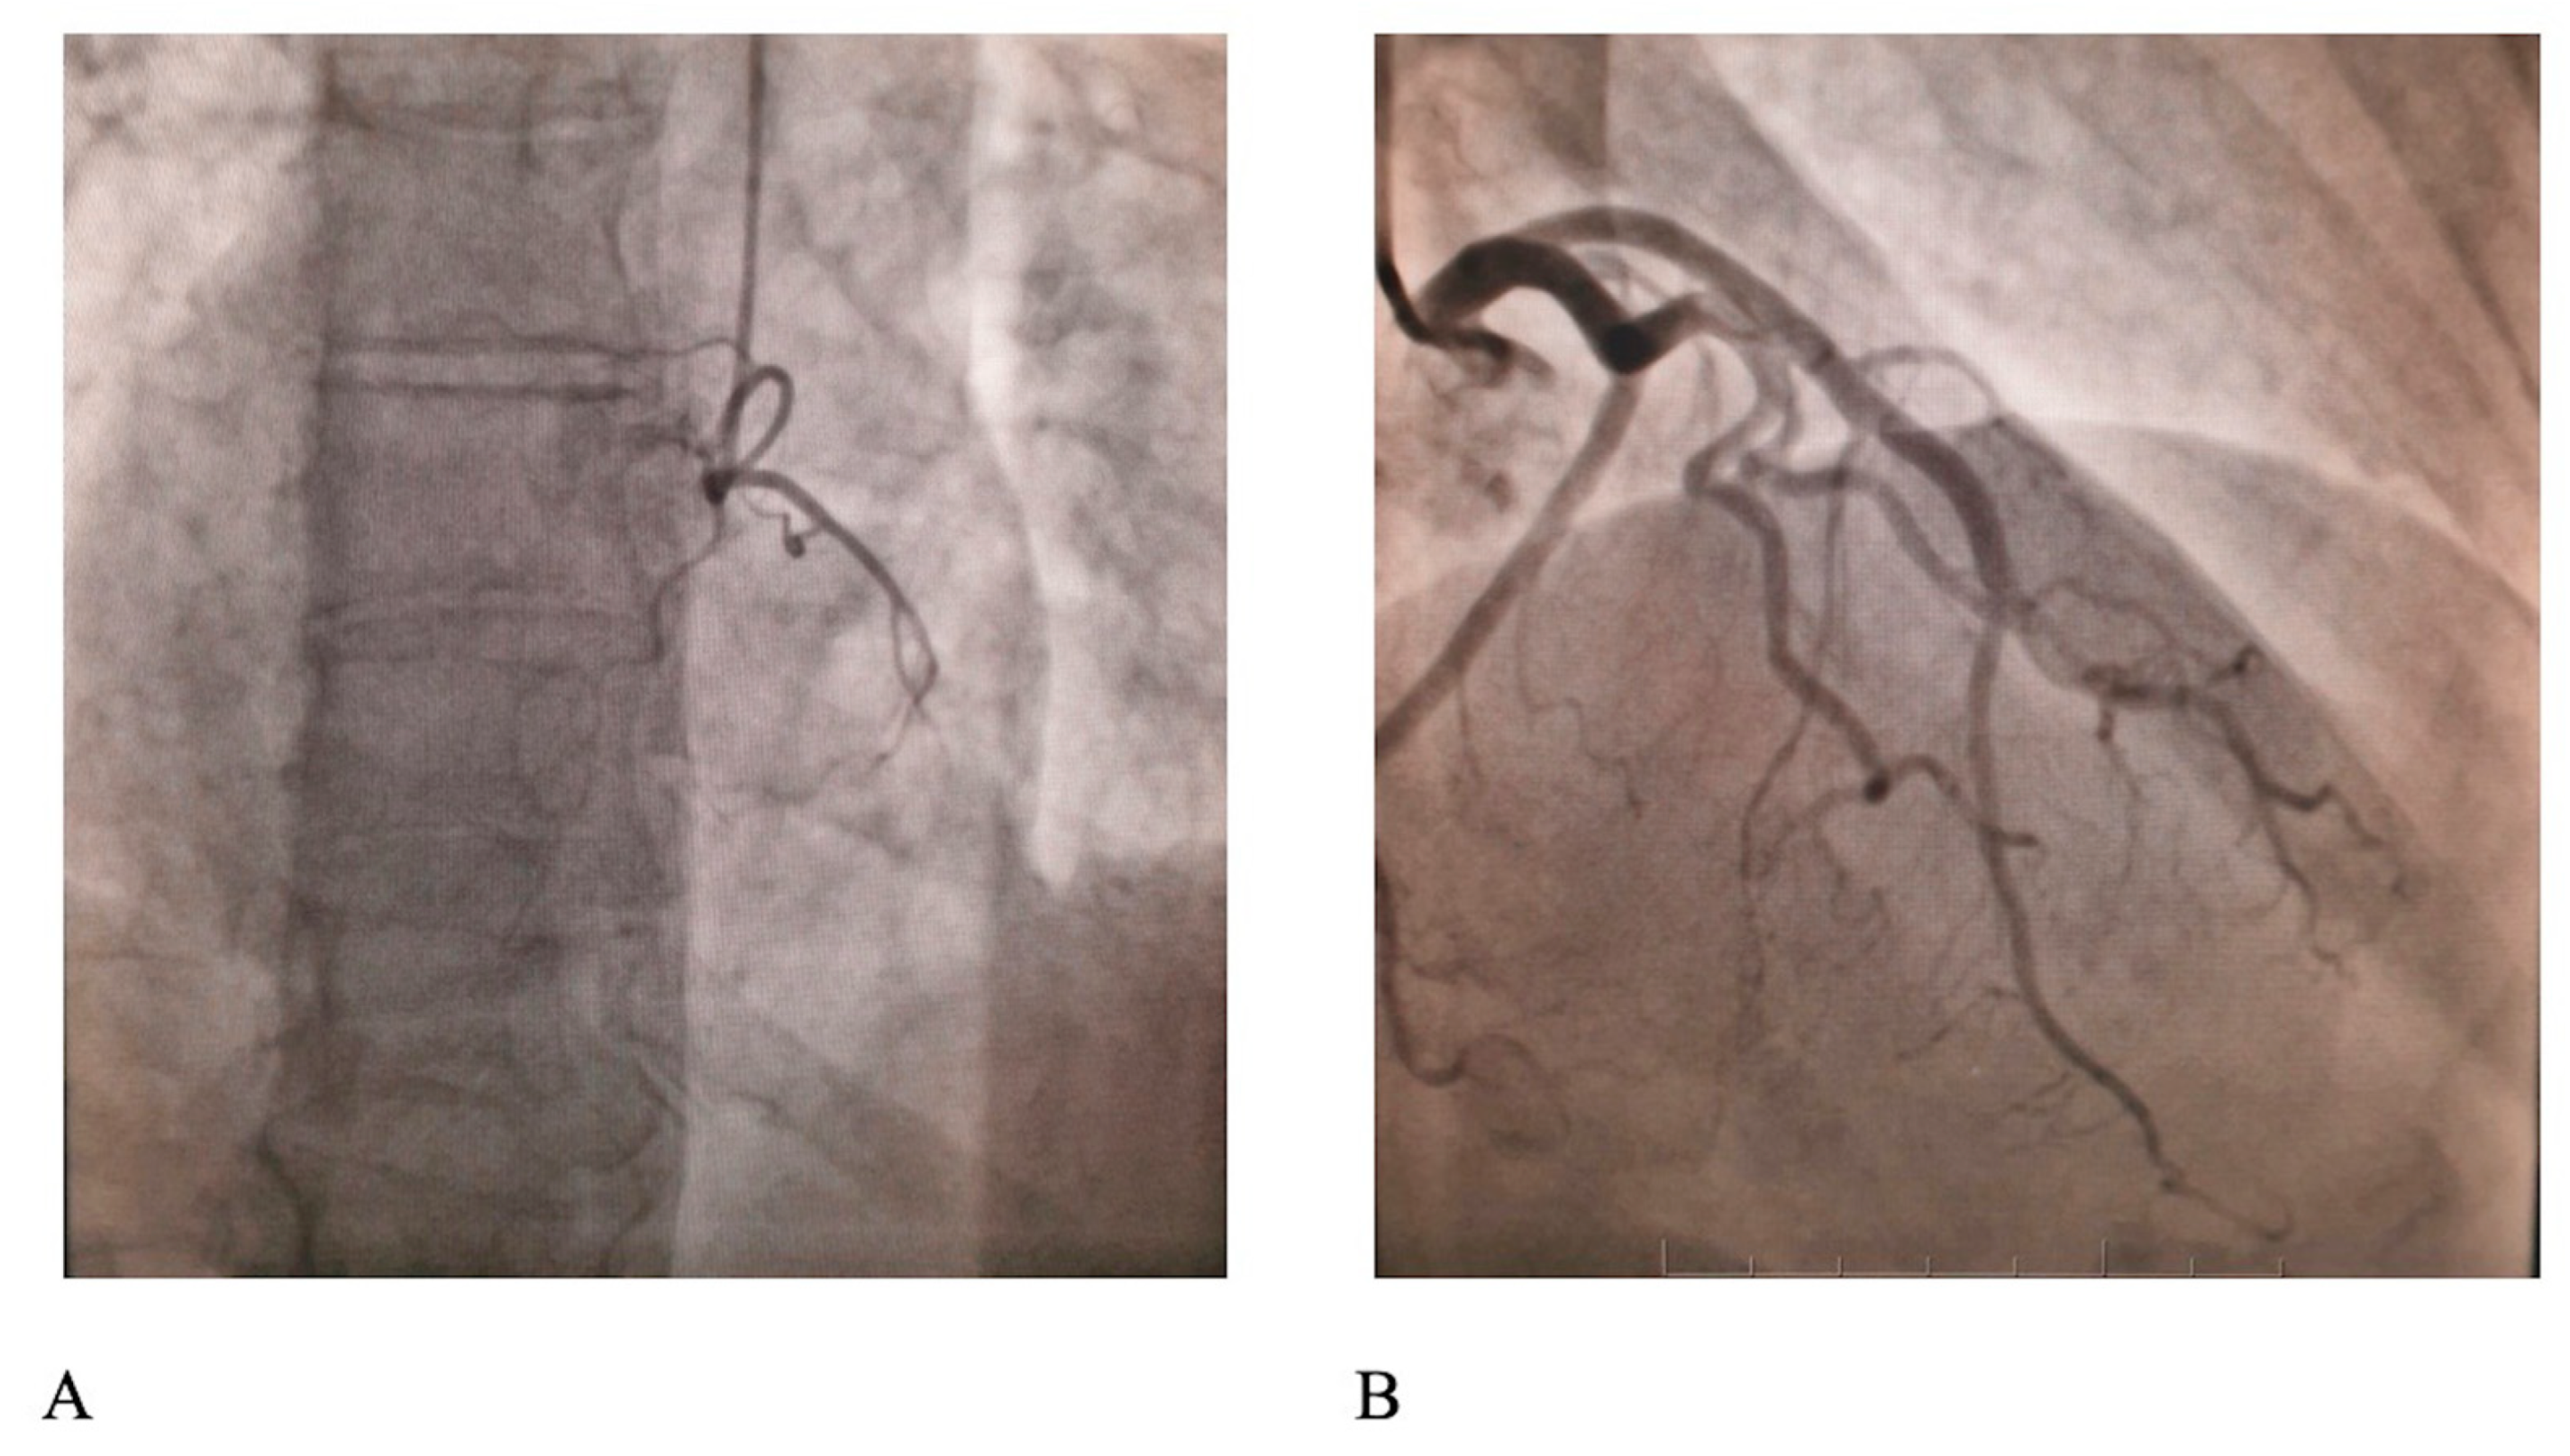

The troponin I level was 3.4 ng/mL initially and reached peak levels after 3 h (10.8 ng/mL). Transthoracic echocardiographic assessment revealed a non-dilated left ventricle with a moderate reduction in the left ventricle ejection fraction (LVEF, 40%) with severe hypokinesis of the apical segments of the anterior and inferior wall. On the same day, on day 3 from the time of admission, the patient underwent a coronary angiogram using the radial approach with a Glidesheath Slender 6 French (F; cat. no. RM*ES6J10SQ, Terumo Europe NV) using iopamidol contrast (Isovue, Bracco Diagnostics Inc.). The engagement of the right and left coronary arteries was achieved with diagnostic 6 F catheters, Judkins left 3.5 (cat. no. RQ-4JL3500M; Terumo Europe NV) for the left coronary artery and Judkins right 4.0 (RQ-4JR4000M, Terumo Europe NV) for the right artery, on a Siemens Artis zee angiography system (Siemens). The acquisition of at least three incidences for the right coronary artery and at least four for the left coronary artery did not reveal any notable lesions at the level of the epicardial arteries (Figure 2).

The diagnosis of stress cardiomyopathy or TTC was established based on the Mayo Clinic criteria [12] and also by considering earlier expert consensus, namely the 2018 International Takotsubo Diagnostic Criteria [13,14], this being one of the entities included under the umbrella of myocardial infarction with non-obstructive coronary arteries (MINOCA). Various differential diagnosis from the MINOCA, seen as Pandora’s box, were considered in the case of our patient, such as myocarditis, type 2 myocardial infarction or other cardiomyopathies. The lack of cardiac magnetic resonance modifications suggestive for myocardial infarction or Lake Louis myocarditis criteria sustained TTC diagnosis. Supportive treatment with fluid resuscitation was administered (250 mL isotonic saline solution for 15 min, aspirin 75 mg daily, statins (atorvastatin at 80 mg once per day) and continuous noradrenaline infusion at an average dose of 0.5 µg/kg/min for ~12 h followed by progressive dose reduction until discontinuation on the following day); the previously mentioned treatment allowed for hemodynamic improvement on day 6 after drug poisoning. Echocardiographic assessment on day 6 revealed complete recovery of the LVEF with normal wall motion and the patient was discharged on day 8. At the 3-month follow-up, the patient remained asymptomatic whilst being evaluated twice a month in the psychiatric out-patient clinic for a depressive disorder requiring fluoxetine 20 mg daily and cognitive behavioral therapy twice a week.

Figure 2. Coronary angiogram displaying normal (A) right and (B) left coronary arteries.